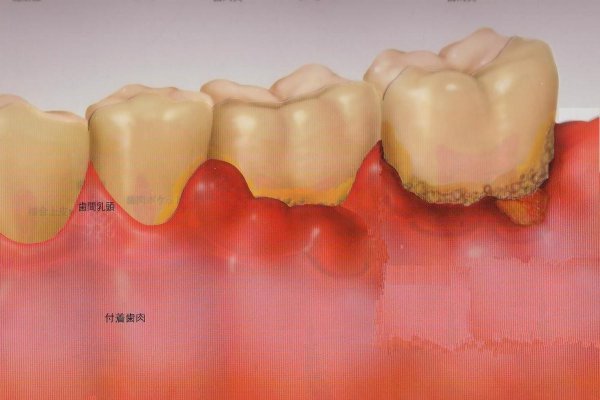

歯周病の原因と進行 山形県東根市の歯医者 森歯科クリニック

歯周病とは 小林歯科医院 野洲市 小篠原の歯医者 歯科